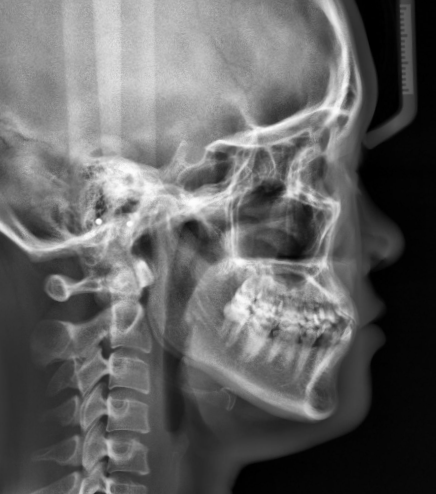

这位女生主诉自己门牙缝隙大,牙齿不齐,“地包天”面型,想通过牙齿矫正调整牙齿问题和改善面型美观。通过牙片资料检查发现,骨性III类倾向,上颌发育不足,下颌颏部前突,鼻基底凹陷,前牙2-2缺失,中线不齐,个别牙反颌。

考虑到门牙有缝,前牙2-2缺失,在加上鼻基底部比较塌,上颌拔牙的话容易导致更塌更瘪,进一步影响面型美观。因此制定不拔正畸牙,推磨牙向远中矫正方案,关闭门牙缝隙,采用隐形牙套控制牙根往外推,牙冠往里内收,这样上牙会变得更直一些,面型会变得相对饱满。

矫正前上牙是往外唇倾的时候,她的垂直高度是短的,笑的时候是露不出上牙的,就容易显得老、显得瘪,所以上牙要伸长。

因此遇到这种面型情况,我们要让根往外唇向移动、冠往舌向移动,同时垂直向伸长,如果做到这些操作,上牙就会显得饱满一些。

那接下来我们要考虑到下颌的问题,我们要让她的上后牙压低,下后牙升高,要给下颌向后退,创造出一个向后退的轨道,下牙我们要做好控根移动,那这个时候面型因此就会变得相对会好看一些。